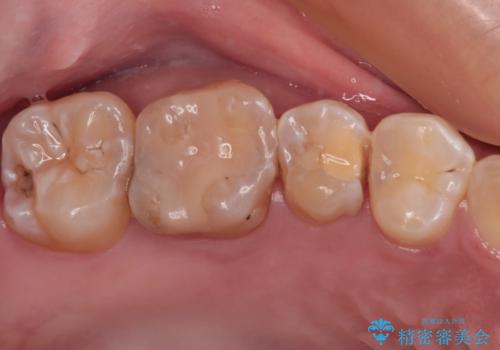

- 以前詰め物をした奥歯に物が頻繁に挟まるとのことで来院された患者様です。

充填物は形態が不正であり、歯肉付近にバリのように充填材料が飛び出していたため、歯肉が腫れやすい状態でした。

精密に治療を行うため、型取りを行った上でセラミックインレーによる修復治療を行うこととしました。